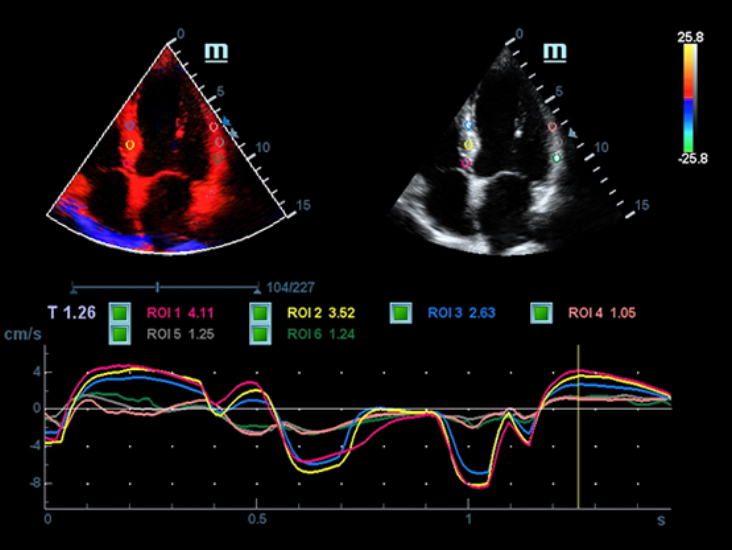

–°–Ņ–Ķ—Ü–ł–į–Ľ–ł–∑–ł—Ä–ĺ–≤–į–Ĺ–Ĺ—č–Ļ —É—Ö–ĺ–ī –Ī–Ľ–į–≥–ĺ–ī–į—Ä—Ź ECHO

–°–ĺ–≤–ľ–Ķ—Ā—ā–Ĺ–ĺ —Ā —Ā–ĺ–≤—Ä–Ķ–ľ–Ķ–Ĺ–Ĺ—č–ľ–ł —É–Ľ—Ć—ā—Ä–į–∑–≤—É–ļ–ĺ–≤—č–ľ–ł —ā–Ķ—Ö–Ĺ–ĺ–Ľ–ĺ–≥–ł—Ź–ľ–ł –Ĺ–ĺ–≤–ĺ–Ķ —Ä–Ķ—ą–Ķ–Ĺ–ł–Ķ –ĺ—ā Mindray –Ņ—Ä–Ķ–ĺ–Ī—Ä–į–∑—É–Ķ—ā –į–ļ—ā—É–į–Ľ—Ć–Ĺ—č–Ķ –∑–į–ī–į—á–ł –ļ–Ľ–ł–Ķ–Ĺ—ā–ĺ–≤ –≤ –ļ–Ľ–ł–Ĺ–ł—á–Ķ—Ā–ļ–ł–Ķ –Ņ–ĺ—ā—Ä–Ķ–Ī–Ĺ–ĺ—Ā—ā–ł. –ü–ĺ—Ā—ā–ĺ—Ź–Ĺ–Ĺ–ĺ —Ä–į–∑–≤–ł–≤–į—Ź—Ā—Ć, —ć—ā–į —Ā–ł—Ā—ā–Ķ–ľ–į —Ā–ĺ—á–Ķ—ā–į–Ķ—ā –≤ —Ā–Ķ–Ī–Ķ —Ā—ā—Ä–Ķ–ľ–Ľ–Ķ–Ĺ–ł–Ķ –ļ –Ĺ–Ķ–ĺ–≥—Ä–į–Ĺ–ł—á–Ķ–Ĺ–Ĺ—č–ľ –≤–ĺ–∑–ľ–ĺ–∂–Ĺ–ĺ—Ā—ā—Ź–ľ –ł –∂–Ķ–Ľ–į–Ĺ–ł–Ķ –∑–į–≥–Ľ—Ź–Ĺ—É—ā—Ć –≤ –Ī—É–ī—É—Č–Ķ–Ķ.

–ú–Ĺ–ĺ–≥–ĺ—Ą—É–Ĺ–ļ—Ü–ł–ĺ–Ĺ–į–Ľ—Ć–Ĺ–į—Ź —Ā–ł—Ā—ā–Ķ–ľ–į DC-60 Exp —Ā X-Insight –Ņ—Ä–Ķ–ī—Ā—ā–į–≤–Ľ—Ź–Ķ—ā —Ā–ĺ–Ī–ĺ–Ļ –ļ–ĺ–ľ–Ņ–Ľ–Ķ–ļ—Ā–Ĺ–ĺ–Ķ —Ä–Ķ—ą–Ķ–Ĺ–ł–Ķ, –ļ–ĺ—ā–ĺ—Ä–ĺ–Ķ –Ņ–ĺ–ľ–ĺ–≥–į–Ķ—ā —É–Ņ—Ä–į–≤–Ľ—Ź—ā—Ć –Ņ–ĺ–≤—Ā–Ķ–ī–Ĺ–Ķ–≤–Ĺ–ĺ–Ļ –ļ–Ľ–ł–Ĺ–ł—á–Ķ—Ā–ļ–ĺ–Ļ –Ņ—Ä–į–ļ—ā–ł–ļ–ĺ–Ļ —Ā –Ľ–Ķ–≥–ļ–ĺ—Ā—ā—Ć—é –ł —É–≤–Ķ—Ä–Ķ–Ĺ–Ĺ–ĺ—Ā—ā—Ć—é.

–ě—Ā–Ĺ–ĺ–≤—č–≤–į—Ź—Ā—Ć –Ĺ–į –≥–Ľ—É–Ī–ĺ–ļ–ĺ–ľ –Ņ–ĺ–Ĺ–ł–ľ–į–Ĺ–ł–ł –Ņ–ĺ—ā—Ä–Ķ–Ī–Ĺ–ĺ—Ā—ā–Ķ–Ļ –ļ–Ľ–ł–Ķ–Ĺ—ā–ĺ–≤, –ļ–ĺ–ľ–Ņ–į–Ĺ–ł—Ź Mindray —Ä–į–∑—Ä–į–Ī–ĺ—ā–į–Ľ–į —Ā–ł—Ā—ā–Ķ–ľ—É DC-60 Exp —Ā X-Insight, —á—ā–ĺ–Ī—č –ĺ–Ī–Ķ—Ā–Ņ–Ķ—á–ł—ā—Ć –≤—č—Ā–ĺ–ļ—É—é –Ņ—Ä–ĺ–ł–∑–≤–ĺ–ī–ł—ā–Ķ–Ľ—Ć–Ĺ–ĺ—Ā—ā—Ć –ł —ā–ĺ—á–Ĺ–ĺ—Ā—ā—Ć –≤–ł–∑—É–į–Ľ–ł–∑–į—Ü–ł–ł –≤–ļ—É–Ņ–Ķ —Ā –Ĺ–į–≥–Ľ—Ź–ī–Ĺ–ĺ—Ā—ā—Ć—é, –ł—Ā–ļ–Ľ—é—á–ł—ā–Ķ–Ľ—Ć–Ĺ–ĺ–Ļ –ł–Ĺ—ā–Ķ–Ľ–Ľ–Ķ–ļ—ā—É–į–Ľ—Ć–Ĺ–ĺ—Ā—ā—Ć—é –ł –ĺ–≥—Ä–ĺ–ľ–Ĺ—č–ľ –ĺ–Ņ—č—ā–ĺ–ľ.